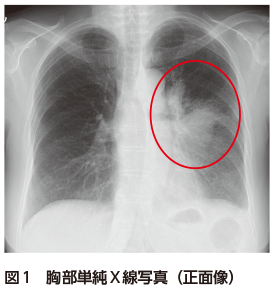

胸部単純X線写真では左上中肺野縦隔側に広範な浸潤影を認める(図1).胸部CTでは左上葉に,中枢から拡がる浸潤影を認め,周囲にすりガラス影を伴う(図2).胸部CT縦隔条件では,中枢気管支内に粘液栓を認め,内部のCT値が上昇している図3).いわゆる高吸収粘液栓(high attenuation mucus:HAM)の所見である.

ABPMは気道内に定着した真菌によって発症する慢性炎症性気道疾患であり,Ⅰ型・Ⅲ型アレルギー反応が関与している.真菌感染症とは異なり真菌の組織浸潤は認められず,菌体は気管支内粘液栓に限局している1)Aspergillus fumigatusが原因として最も多く,アスペルギルスが原因の場合にはABPAと呼ばれる.ABPMの特徴的な画像所見として,気管支内を充填する粘液栓・中枢性気管支拡張がある.約25%の症例では,真菌が酸化物として産生する鉄やマンガン,カルシウムが高吸収域(CT値で70 HU以上)として認識され,HAMとなる2)好酸球性肺炎を合併した例では,粘液栓の末梢に浸潤影やすりガラス影を認める2)